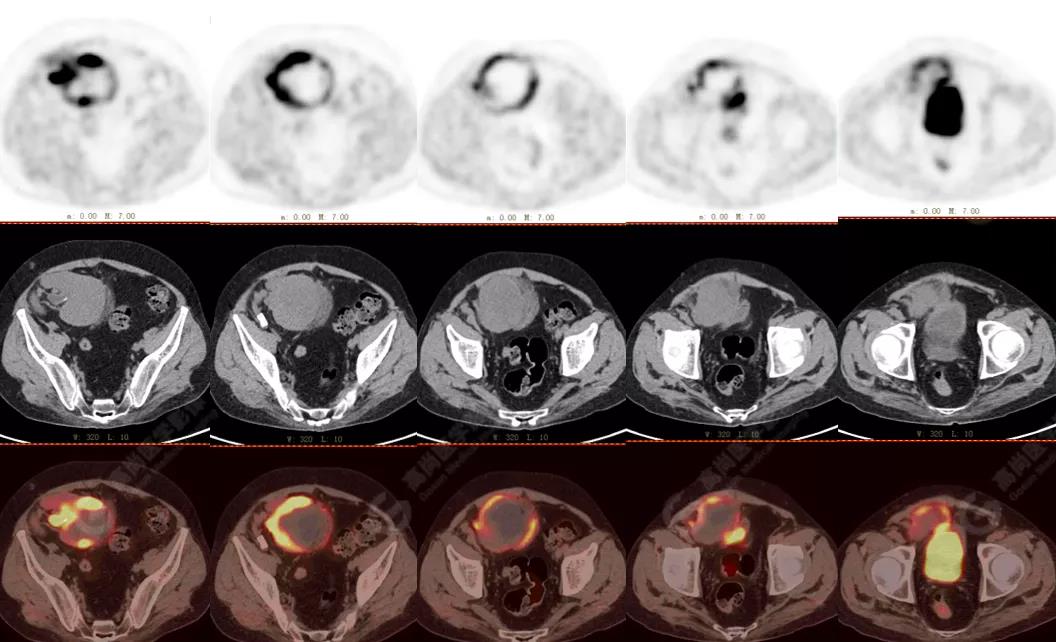

PET/CT檢查

↑移植腎下部等密度腫塊,代謝環(huán)狀增高,SUVmax13.4,中心代謝缺損

PET/CT檢查意義

發(fā)現(xiàn)全身其它部位有無結(jié)內(nèi)或結(jié)外淋巴瘤病灶。由于淋巴瘤組織多具備高代謝、大范圍無氧酵解的特性,葡萄糖需求量為正常組織細(xì)胞的20~30倍,正電子湮滅產(chǎn)生的光子信號聚集于灶區(qū),PET捕獲后可半定量分析其分布特征【4】。

PET/CT融合二者各自優(yōu)勢

將影像學(xué)技術(shù)提高到分子水平,結(jié)合以腫瘤形態(tài)學(xué)、解剖學(xué)、代謝學(xué)特征,對DLBCL細(xì)胞增殖、生長或凋亡可作出有效判斷,還可為檢驗(yàn)治療有效性與預(yù)后療法優(yōu)化提供指導(dǎo)【4】。